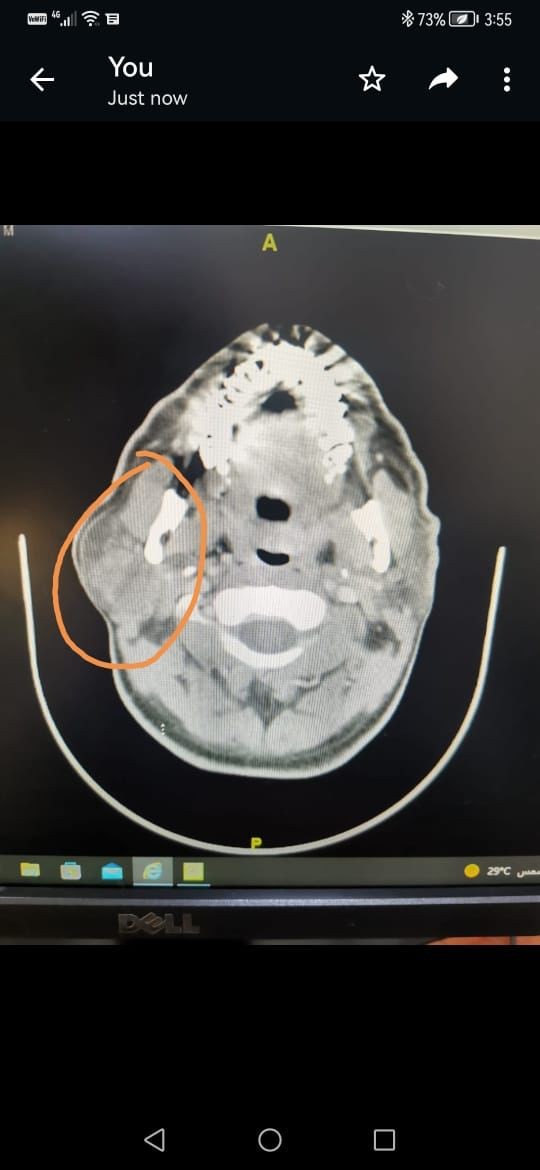

تمكن فريق من الجراحين بمجمع الملك فيصل الطبي بالطائف من استئصال ورم حميد في الغدة النكافية اليمنى لمريض خمسيني، حيث تمت معاينة المريض من قِبل فريق طبي من الاستشاريين المتخصّصين بقيادة الدكتور شكيل احمد والدكتور عادل سليمان والدكتورة آسر والدكتور سرفراس رسيل والدكتور صالح الزهراني، وتبيّن أنه يعاني من ورم حميد، وبعد إجراء الفحوص المعملية والإشعاعية المناسبة تقرّرت الخطة الجراحية المتقدمة والتي تحتاج الى إجراء جراحي للغدة النكافية، وقد استغرقت العملية ثلاث ساعات وتكللت ولله الحمد بالنجاح.

وتعد هذه العملية من العمليات النوعية بسبب ارتباط الغدة النكافية بخمسه فروع من العصب الوجهي وحيث إنها تحتاج إلى فريق طبي متخصص ذي كفاءة عالية من الجراحين والتخدير والعناية المركزة.